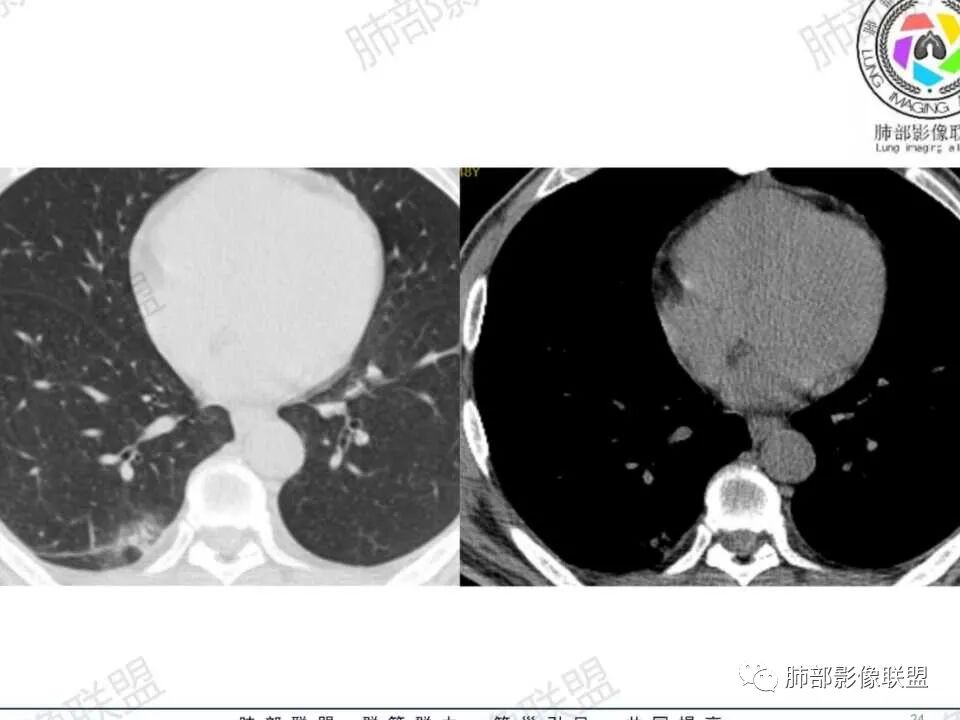

1.中年男性,发现肺部结节增大就医(一年前发现肺部结节),缺乏临床表现。有糖尿病基础。

2.右肺下叶背段指尖大小结节影伴外围片状影及小结节影,片影中有结节感。

3.近背段支气管开口附近结节密度不甚均匀,未见钙化或脂质密度区。边界清楚光整,内侧平直,未见典型深分叶及毛刺,增强扫描轻度强化。

4.哌拉西林、左氧氟沙星等治疗一周后,较大结节影及外围病灶范围均见增大。

5.背段支气管于结节内侧份“旁现侧出”,管壁完整,管腔少量分泌物,近乎疏通状态。结节内隐约出现微小含气空腔。

6.肺门及纵隔未见增大淋巴结。

1.会是肺腺癌吗?较长时间段内固定存在的结节影我们会想到新生物。本例结节影边界清楚光整,内缘平直,缺乏典型深分叶及毛刺,未见异常强化,未见肿大淋巴结等,缺乏肺腺癌的依据。

2.会是硬化性肺细胞瘤吗?病灶支气管相关,未见异常强化,短期内增大等几乎完全将硬化性肺细胞瘤排除在外。

3.同样的理由也不支持错构瘤,尽管结节影密度不均匀。我们几乎不可能在错构瘤中观察到如此穿行的支气管!

4.会是隐球菌感染吗?急性感染,如易形成空洞的肺炎克雷伯杆菌感染等我们自然不在考虑之列,无论是临床表现还是影像学改变。肺部隐球菌病灶有时酷似新生物,但如此漫长不出新花样的侵袭性病灶则非常罕见!

5.临床表现轻微的病灶还有肺结核!可以长期“默默无闻”。本例结节影密度欠均匀,强化不显著,可以出现小空洞,周围见小结节影等,结核确实存在众多支持点。

不事张扬的小空洞,最常见的还是结核!